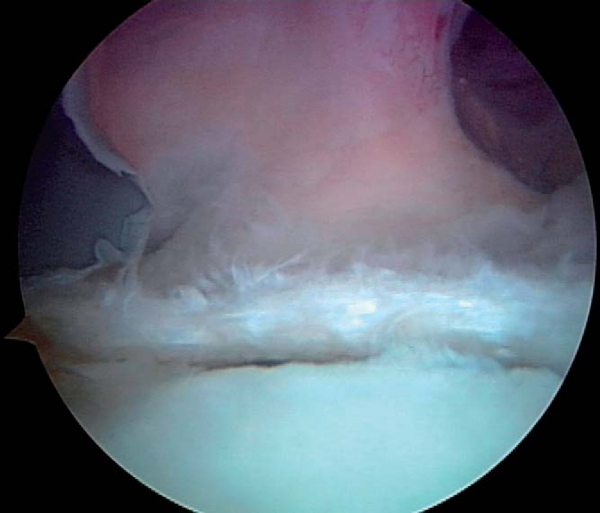

When the posterior labrum is detached, suture anchors are employed in performing the repair. The posterior labrum is visualized from both the posterior and anterior portals to appreciate the full extent of the tear (

Fig. 8-8

| • | The arthroscope then remains in the anterior portal, and the posterior portal serves as the working portal for the repair. | |

Figure 8-8 |